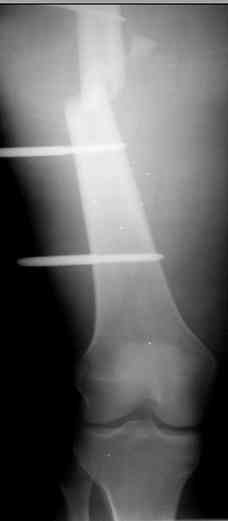

Коллеги! Прошу совета, какую тактику избрать при лечении.Больной 27 лет, мотоциклист. Поступил 23.04.10 ДЗ. О. перелом н.з левого бедра Gustillo 3b (c повреждение бедренной вены), О.Правого бедра Gustillo 2, з. фрагментарный перелом левой голени.При поступлении Hb 66 ISS 40, Фиксация стержневыми аппратами, сосудистые хирурги выполнили шов вены. Выполена резекция бедренной кости 9 см. На 7 сутки Желудочно-кмшечное кроветечение из стрессовых язв, 12 сутки флотирующий тромтоз 14 см установлен кава-фильтр. На 15 сутки закрытие ран местными тканями. Раны заживают первично. Воспаления на стержнях нет. В настоящий момент планируем. Переход со стержневых аппаратов на стержни с антибактериальным покрытием на правом бедре и левой голени. Левое бедро планируем продолжить фиксировать в стержневом аппарате.

Вопрос: что делать с левым бедром? Учитывая внутрисутавной характер перелома, дефект бедра 9 см.

На левом бедре оставили аппарат бедро-голень.

Если у Вас возникнут какие-то сомнения, то возможно наложение гибридного циркулярного-монолатерального дистракционного аппарата на левое бедро и выполнение остеотомии в в/3 бедра. Почему монолатеральный гибридный аппарат, а не аппарат Илизарова? Эта конструкция гораздо легче переносится пациентами, в ней гораздо удобнее проводить местное лечение ран.

Разрешите рассказать о пациенте, которому мы фиксировали перелом такой конструкцией.

Больной 19 ти лет, пострадал в результате ДТП, пассажир мотоцикла. Получил открытый оскольчатый перелом н/3 левой бедренной кости 3a тип по Гастилло-Андерсену. При поступлении ПХО ран, фиксация стержневым аппаратом наружной фиксации. Лечение больного осложнилось развитием анаэробной флегмоны левого бедра. Лампасные разрезы, неоднократные некрэктомии, некротизировался участок диафиза левой бедренной кости на протяжении 15 см. Произведена резекция. 20.05.10- демонтаж АНФ, остеоситез левой бедренной кости гибридным циркулярно-монолатеральным стержневым дистракционным аппаратом наружной фиксации, остетомия левой бедренной кости в в/3. Сейчас начата дистракция в аппарате, проводится подготовка ран к аутодермопастике.